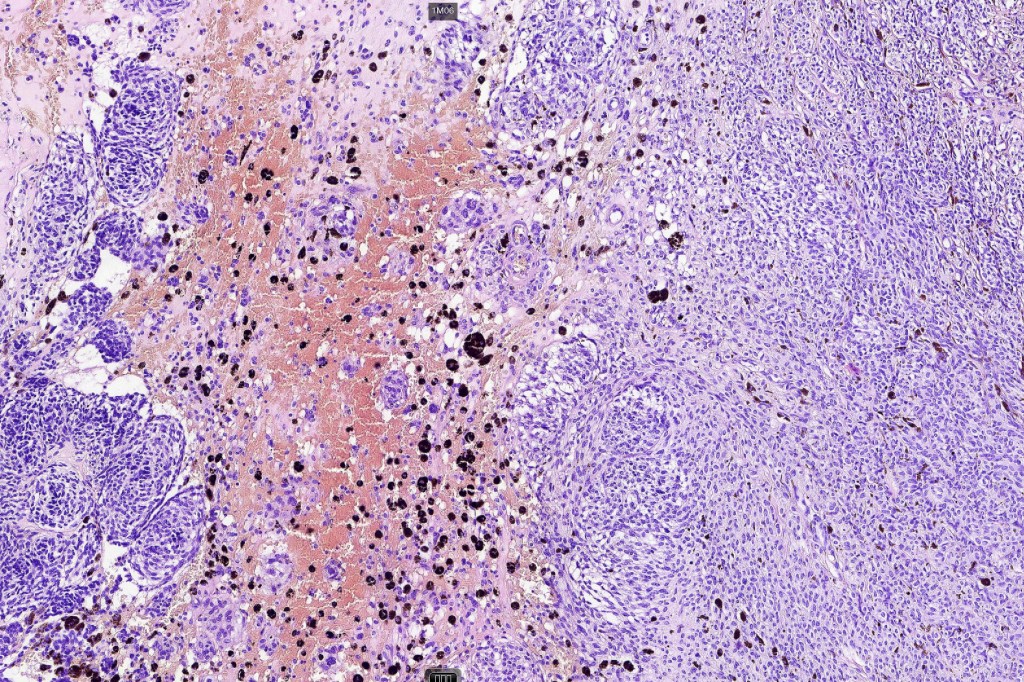

Atpical blue nevus

This is exceedingly rare and the diagnosis should be used very sparingly. It is likely quite benign although very occasionally, a sentinel node biopsy is positive. Great care must be taken to make sure that a blue nevus-like melanoma isn’t missed. It shows the low power features of a blue nevus but high power scrutiny reaveals pleomorphism, nuclear hyperchromatism and increased mitotic activiy (<1 sq mm). Abnormal mitoses are absent as is necrosis. Perineural involvement can be seen but lymphovascular invasion is absent.